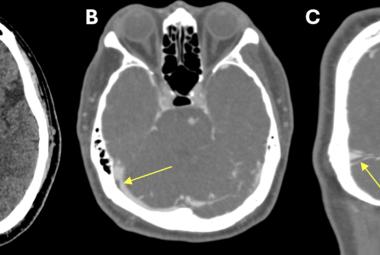

FIGURE 1: Neck re-exploration revealing intact suture at the site of primary repair